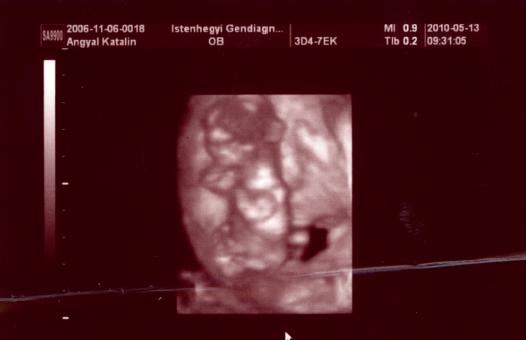

Ahogy a hasamra tette H.K. az uhu fejet, és megjelent a képernyőn a babóm, egyből mondta, hogy szép. A nagy kő legördült a szívemről. Aztán el kezdte méricskélni, és bólogatott nagyokat, és az arcán is láttam a nyugodtságot. Tarkóredőt 1,8 és 1,8-nek mérte, orrcsont is van. A végén azt mondta, hogy teljesen negatív uh alapján, de azért megkérdezte, hogy akarok-e amniócentézist, vagy inkább megszülöm (itt gondolom, a vetélési kockázatra gondolt). Aztán a véreredmény is nagyon jó lett, minden az értékeken belül. A PAPP-A 1,00 MoM, a BHCG 1,66 MoM. Így a két kockázati tényezőmmel együtt (korom + korábbi Down-kór) magasan negatív lett az eredményem, 1:1060-hoz. Ha kivették volna a down kockázatott, közel 1:2000-hez lett volna.

Ma beszkenneltem a babókám képeit, és gondoltam, veletek is megosztom:

Kép

Sajnos a nemét esélyünk sem volt megnézni, mivel végig hason volt, hiába bökdöstük, csak félig volt hajlandó megfordulni, és kibújni a lepényből, és akkor is takargatta a kis ökleivel az arcát. Érdekes, a fiam sosem volt szemérmes az uh-kon :roll:

A mért méretek alapján teljesen megfelel a terhességi kornak, 12+4 (és valóban 1-2 nappal kisebb a baba, mint amit a vonalzóm jelez, mert a 15. vagy 16. napon fogant). 7,04 centis az Óriásgombockám.